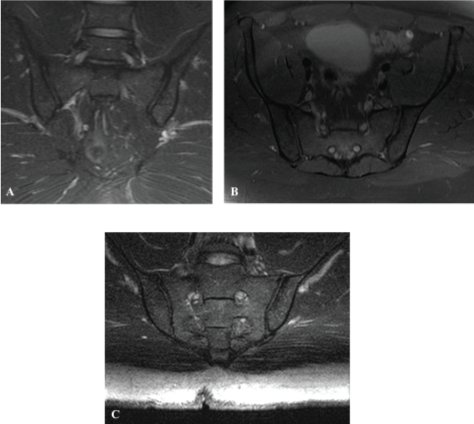

Radial imaging can be subjected to the same common artifacts (e.g., motion, flow, and wrap) that occur in routine scans. It is also exposed to the sequence-specific "cross-talk" artifact, which appears as a hypointense bar-shaped area overlying the superior and/or inferior aspect of the sacrum and iliac bones. This artifact can be explained as follows: All radial imaging planes go through the center of the joint, partially exciting the area of intersection by each selective RF pulse. After the first image is obtained, each successive image includes spins that have already been partially saturated, which affects the contrast in the center of the FOV and results in the appearance of an area of low signal intensity known as a cross-talk artifact [10,16,28]. The width of a cross-talk artifact is related to the space between sections; the closer the sections are, the broader the artifact. We have found that obtaining sections at 6º intervals while increasing the FOV to 26 allowed the cross-talk artifact to be present out of the region of interest. We also recommend that in clinical practice, an advanced MRI specialist with knowledge of system specifications and artifact minimization should plan the radial MRI sequence. Furthermore, regarding the comparisons between routine/conventional SIJ MRI and the radial sequence, we have collected several images in conjunction with the radial scans for demonstrative reasons only, as the intention of this work was not to replace the routine protocols but to screen for pathology as an additional sequence within the LS protocol (Figure 3). A comparison of both sets of images for the 101 patients would have been advantageous; however, time is an issue, and we were not able to perform this comparison in the present study.

Figure 3: A) Conventional coronal; (B) Axial PD W images and (C) Radial MRI T2-W FS images of the SIJ. These images are used for comparison between routine/conventional SIJ MRI and the radial sequence and were used for demonstrative purposes only, as the intention of this work was not to replace the routine protocols but to screen for pathology as an additional sequence within the LS protocol.  View Figure 3